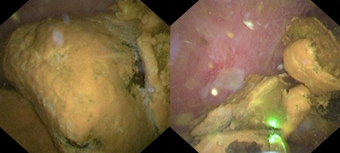

◆거대 담관결석(좌)과 홀뮴레이저로 효과적으로 분쇄된 모습(우)